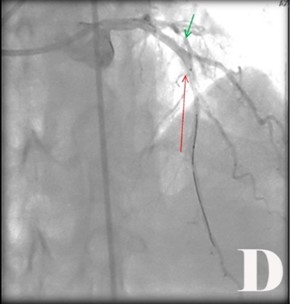

Fig. Abordaje invasivo emergente en paciente con Angina inestable de Alto riesgo y cambios electrocardiográficos atípicos con FEVI muy baja.

Fig. Se visualizó obstrucciones largas proximal y distal de 90 % de coronaria derecha (CD) (2A). Se realizó ACTPs y coloco 2 Stens convencionales (2B). Obstrucción de tercio proximal de 90 % de arteria coronaria de descendente anterior (DA) y del 95 % de la circunfleja izquierda (CX) (2C), se le realizó ACTP y colocó Stens a la DA fármacoactivo pero por el riego-beneficio se decidió no hacer nada en CX (2D).